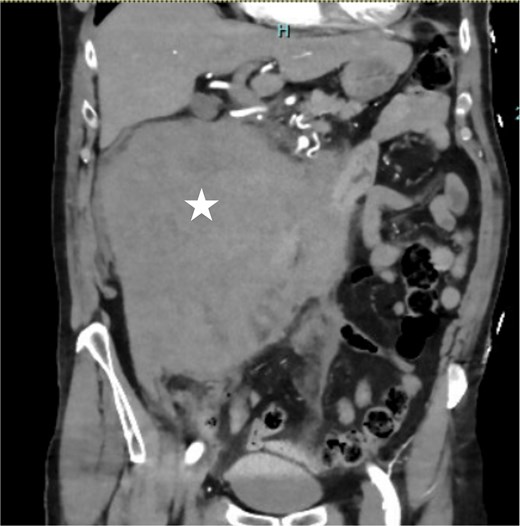

A 73-year-old man presented to the Emergency Department with acute onset right-sided abdominal pain and a syncopal episode. He has no significant past medical history and is not on anticoagulation. On presentation, he was hemodynamically stable with heart rate of 70, blood pressure 113/75, respiratory rate 12, oxygen saturation 95% on room air and afebrile. His hemoglobin (Hb) is 119 and coagulation studies were normal. The computed tomographic (CT) angiography (Fig. 1) of the abdomen demonstrated a large retroperitoneal hematoma measuring 19 cm in width. No active extravasation was identified on the arterial phase. He was managed conservatively with observation and was discharged after three days as he was clinically stable with no change in Hb level.

Coronal contrast-enhanced CT demonstrating a massive right-sided retroperitoneal hematoma (asterisk).